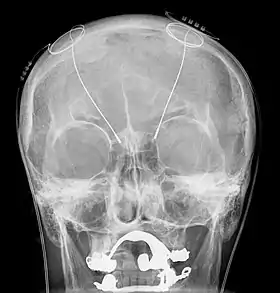

The DBS system consists of three components: the implanted pulse generator (IPG), the lead, and an extension. The IPG is a battery-powered neurostimulator encased in a titanium housing, which sends electrical pulses to the brain that interfere with neural activity at the target site. The lead is a coiled wire insulated in polyurethane with four platinum-iridium electrodes and is placed in one or two different nuclei of the brain. The lead is connected to the IPG by an extension, an insulated wire that runs below the skin, from the head, down the side of the neck, behind the ear, to the IPG, which is placed subcutaneously below the clavicle, or in some cases, the abdomen.[9] The IPG can be calibrated by a neurologist, nurse, or trained technician to optimize symptom suppression and control side effects.[36]

DBS leads are placed in the brain according to the type of symptoms to be addressed. For non-Parkinsonian essential tremor, the lead is placed in either the ventrointermediate nucleus of the thalamus or the zona incerta;[37] for dystonia and symptoms associated with PD (rigidity, bradykinesia/akinesia, and tremor), the lead may be placed in either the globus pallidus internus or the subthalamic nucleus; for OCD and depression to the nucleus accumbens; for incessant pain to the posterior thalamic region or periaqueductal gray; and for epilepsy treatment to the anterior thalamic nucleus.

All three components are surgically implanted inside the body. Lead implantation may take place under local anesthesia or under general anesthesia ("asleep DBS"), such as for dystonia. A hole about 14 mm in diameter is drilled in the skull and the probe electrode is inserted stereotactically, using either frame-based or frameless stereotaxis.[38] During the awake procedure with local anesthesia, feedback from the person is used to determine the optimal placement of the permanent electrode. During the asleep procedure, intraoperative MRI guidance is used for direct visualization of brain tissue and device.[39] The installation of the IPG and extension leads occurs under general anesthesia.[40] The right side of the brain is stimulated to address symptoms on the left side of the body and vice versa.